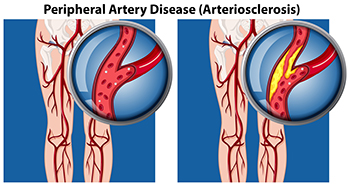

How Peripheral Artery Disease Can Affect the Feet

Peripheral artery disease, abbreviated PAD, also referred to as peripheral vascular disease, is a condition that arises from the reduced flow of blood to the body’s extremities, including the lower legs and feet. People with diabetes are more susceptible to developing PAD, as a result of weakened and damaged blood vessels from having high blood sugar. Blood clot formation within the vessels can also contribute to this condition. Conditions such as arthritis, which causes inflammation of the arteries, can further fuel peripheral artery disease. Other factors, such as smoking, hypertension, and obesity, increase the risk of developing PAD. Symptoms can include intermittent pain, coldness, numbness, and a bluish hue in the skin. In more advanced stages, wounds that resist healing, and areas of skin that blacken may develop due to the lack of adequate blood flow. In such cases, swift medical intervention is extremely important. If you suspect you may have peripheral artery disease that is affecting your lower extremities, it is suggested that you make an appointment with a podiatrist, who is specifically trained to manage this condition.

Peripheral artery disease can pose a serious risk to your health. It can increase the risk of stroke and heart attack. If you have symptoms of peripheral artery disease, consult with one of our podiatrists from James Kutchback, DPM, CWS-P. Our doctors will assess your condition and provide you with quality foot and ankle treatment.

Peripheral artery disease (PAD) is when arteries are constricted due to plaque (fatty deposits) build-up. This results in less blood flow to the legs and other extremities. The main cause of PAD is atherosclerosis, in which plaque builds up in the arteries.

Symptoms

Symptoms of PAD include:

- Claudication (leg pain from walking)

- Numbness in legs

- Decrease in growth of leg hair and toenails

- Paleness of the skin

- Erectile dysfunction

- Sores and wounds on legs and feet that won’t heal

- Coldness in one leg

It is important to note that a majority of individuals never show any symptoms of PAD.

Diagnosis

While PAD occurs in the legs and arteries, Podiatrists can diagnose PAD. Podiatrists utilize a test called an ankle-brachial index (ABI). An ABI test compares blood pressure in your arm to you ankle to see if any abnormality occurs. Ultrasound and imaging devices may also be used.

Treatment

Fortunately, lifestyle changes such as maintaining a healthy diet, exercising, managing cholesterol and blood sugar levels, and quitting smoking, can all treat PAD. Medications that prevent clots from occurring can be prescribed. Finally, in some cases, surgery may be recommended.

Peripheral Artery Disease

Peripheral artery disease (PAD), or peripheral arterial disease, is a circulatory problem in which there is a reduction of blood flow to the limbs due to narrowed arteries. When peripheral artery disease develops, the extremities do not receive enough blood flow; this may cause symptoms to develop such as claudication, or leg pain when walking. The legs are the most common site of peripheral artery disease.

Claudication, or leg pain when walking, is one of several symptoms that can develop due to peripheral artery disease. Other symptoms caused by the disease include painful cramping in the hips, thighs, or calves after certain activities; leg numbness or weakness; coldness in the lower leg or foot; sores on the lower extremities that do not heal; hair loss on the lower extremities; and a missing or weak pulse in the lower extremities. In more severe cases, pain may even occur when the body is at rest or when lying down.

Peripheral artery disease is typically caused by atherosclerosis, a condition in which fatty deposits build up in the arterial walls and reduce blood flow. Smoking, diabetes, obesity, high blood pressure, and high cholesterol are some of the risk factors for peripheral artery disease.

If you are experiencing pain, numbness, or other symptoms in the lower extremities, see your healthcare professional immediately. Diagnosed peripheral artery disease can be treated with various medications, angioplasty and surgery, exercise programs, or alternative medicine. It is important to consult a healthcare professional to determine the best treatment for you.